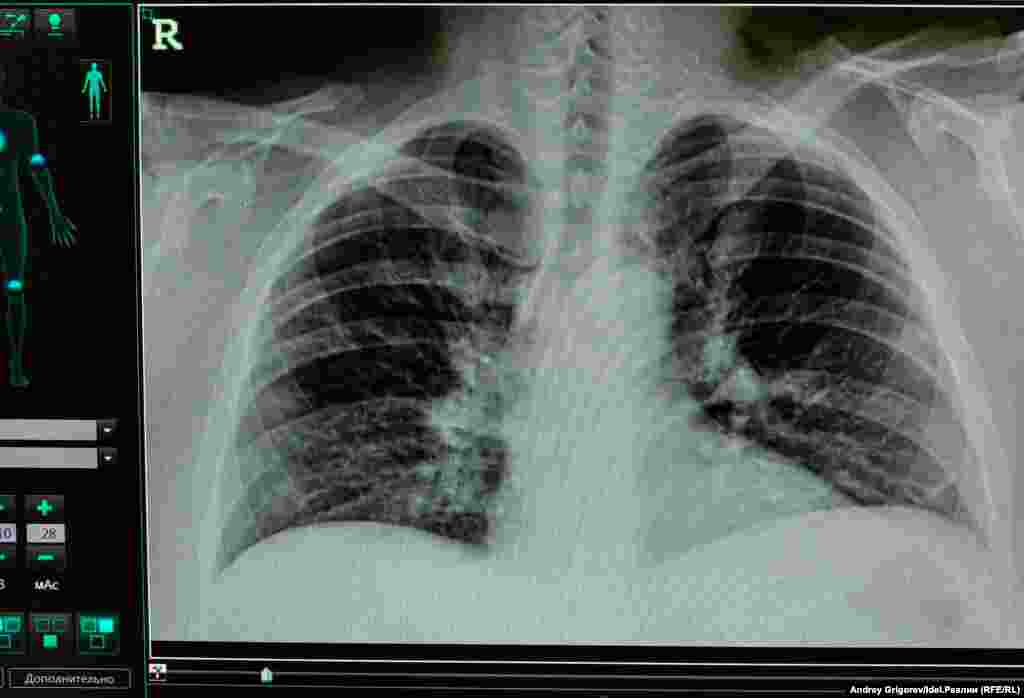

Временный ковидный госпиталь при РКБ является резервным и занимает здание отделения травматологии. Корреспондент Idel.Реалии находился в нем с 4 по 17 июля.